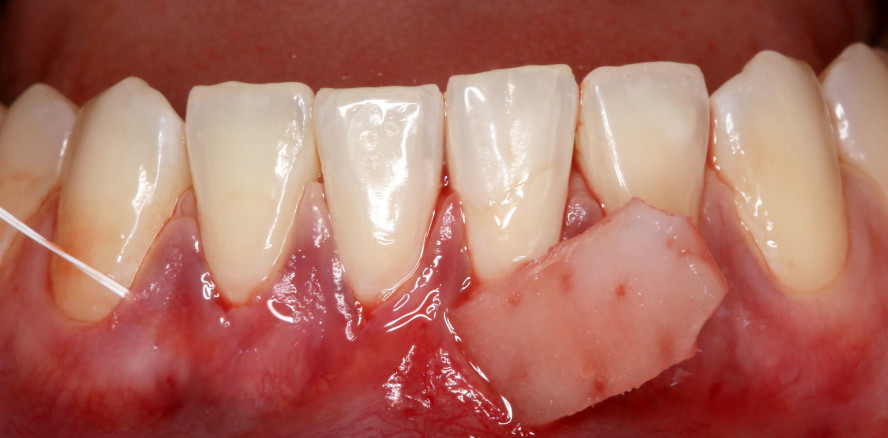

Eine weitere Technik, die zu Unrecht als sehr invasiv bezeichnet wird, ist das freie Schleimhauttransplantat. Die Indikation für diese Technik kann auf wenige Situationen reduziert werden: zum einen die Unterkieferfront mit Rezessionen um Zähne, mit eher dünnem Phänotyp und fehlender attached Gingiva, zum anderen in Situationen ohne attached Mukosa um Implantate im Unterkiefer vor oder nach prothetischer Versorgung. Im Oberkiefer lässt sich die fehlende attached Mukosa in der Regel durch eine Verschiebeplastik im Rahmen der Freilegung etablieren.

In allen Fällen werden autologe Transplantate vom Gaumen gewonnen. Zur Gewinnung eines BGT stehen zwei Grundtechniken zur Verfügung: die Gewinnung als subepitheliales Transplantat z. B. durch eine Single-Inzision oder Trap-Door-Technik sowie als FST, das anschließend deepithelisiert wird.5 Die Gewebe, die hierdurch gewonnen werden, unterscheiden sich jedoch deutlich voneinander.6

Deepithelisiertes FST

In den oberen Schichten finden sich kaum Drüsen- und Fettgewebe. Das gewonnene Transplantat ist sehr kompakt und besteht fast vollständig aus Bindegewebe.

Der Unterschied ist auch intra- und postoperativ zu erkennen. Zum einen unterscheiden sich die beiden BGT’s im Handling. Im Heilungsverlauf unterliegt das subepitheliale BGT einer größeren Schrumpfung, wohingegen das deepithelisierte FST mit der Zeit sogar dazu tendiert, etwas zu proliferieren.